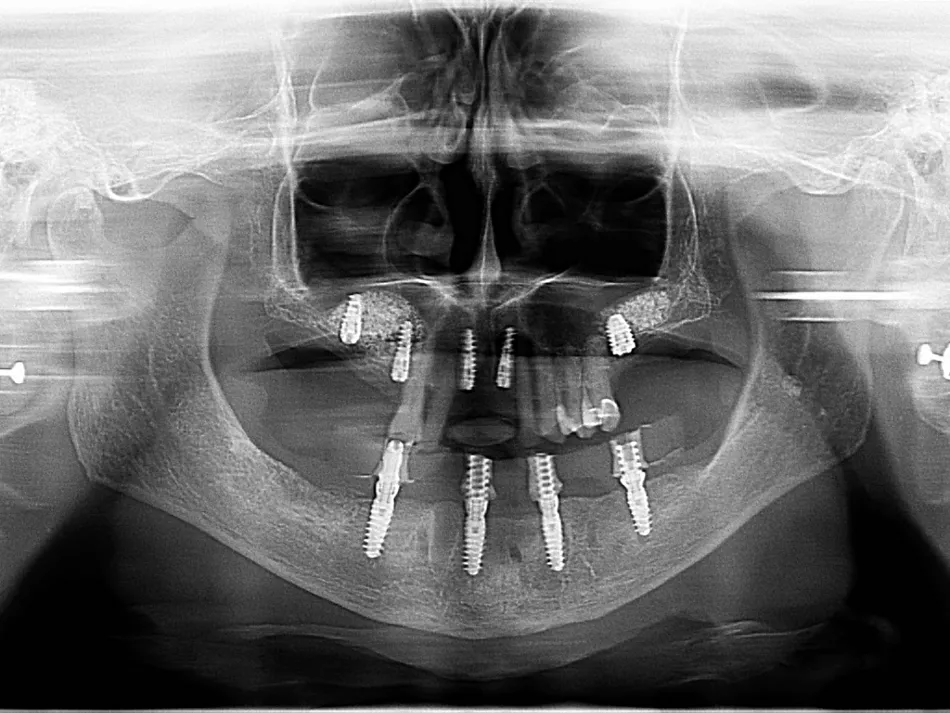

12.  The postoperative OPG shows the implant placement as planned

17.  Final control OPG with the complete treatment of the upper and lower jaw.